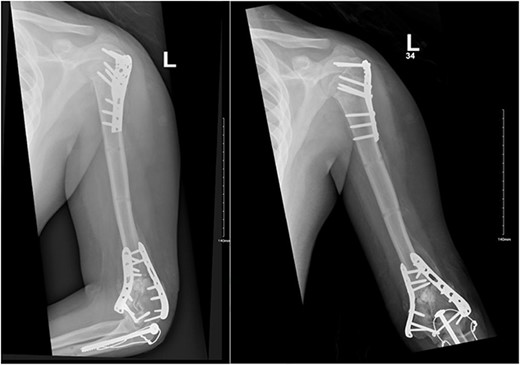

Upon arrival the patient underwent exploratory laparotomy followed by irrigation and debridement of both femur and humerus and application of external fixators (Fig. 2). The patient was admitted to the intensive care unit (ICU). Two days later, the patient underwent open reduction and internal fixation of both proximal and distal humerus (Fig. 3).

Anteroposterior (AP) view of the left humerus and elbow after ORIF.

The patient underwent left open reduction and internal fixation of proximal and distal humerus under general anesthesia. The patient was placed in the lateral position. Preparation and draping in the usual sterile manner were performed and a sterile tourniquet was used. The distal humerus was first approached through a posterior approach. Ulnar nerve protection and olecranon osteotomy was done, showing simple distal intraarticular fracture with minimal metaphyseal comminution. Anatomical reduction of the articular fracture was achieved, with preliminary fixation by k-wires holding the intra-articular fragments. This was followed by interfragmentary screw fixation from medial to lateral. Dual plate fixation (posterolateral and medial anatomical plates) was used to fix both medial and lateral columns, connecting the articular fragment to the metaphyseal. Reduction was confirmed under x-ray. Joint was tested for any screw penetration, and none was found. The osteotomized olecranon was reduced and fixed with cannulated screws and tension bands. The ulnar nerve was protected throughout the whole procedure and was reduced back into the cubital tunnel. Range of motion was examined; full range of motion was achieved. Finally, closure was done in layers.

The patient was then shifted from lateral to beach-chair position, and preparation and draping were repeated. A deltopectoral approach was utilized reaching to the proximal humerus. Reduction was achieved, followed by preliminary fixation with k-wires. Philos plates were used to fix the fracture. Range of motion was examined afterward, with no struggles detected. Fluoroscopic images were taken later to make sure no screws had penetrated the joint. Closure in layers was done, followed by dressing and application of an arm sling.